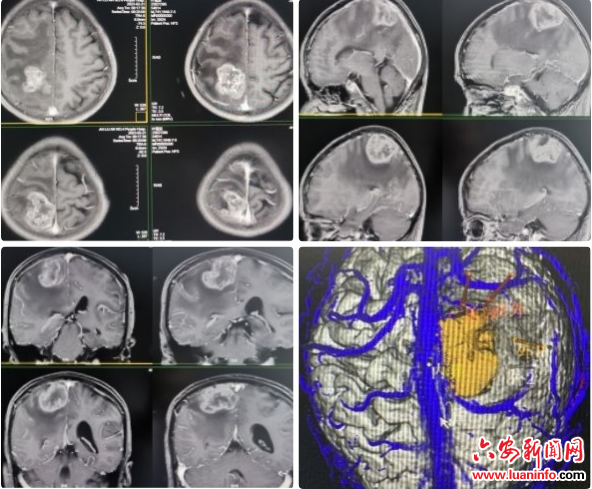

市四院精准智能诊疗迈入新高地 ——六安首例神经外科手术机器人辅助脑肿瘤切除手术

工欲善其事,必先利其器。为更好地服务金安区及周边县区患者,安徽医科大学第二附属医院六安院区、六安市第四人民医院引进神经外科手术机器人,并在皖西地区率先开展神经外科手术机器人手术,自此皖西地区迈入精准化、智能化、微创化机器人新高地。 神经外科创新手术机器人具有先进的视觉定位、颅内血管重建、智能避障及力传感等先进技术,可以帮助医生快速定位癫痫病灶、肿瘤边界、出血位置、脑功能区以及制定精准的癫痫、帕金森、颅内肿瘤、脑出血等手术方案。同时,帮助医生根据手术规划进行快速穿刺、引流抽吸、定向定位及电极...